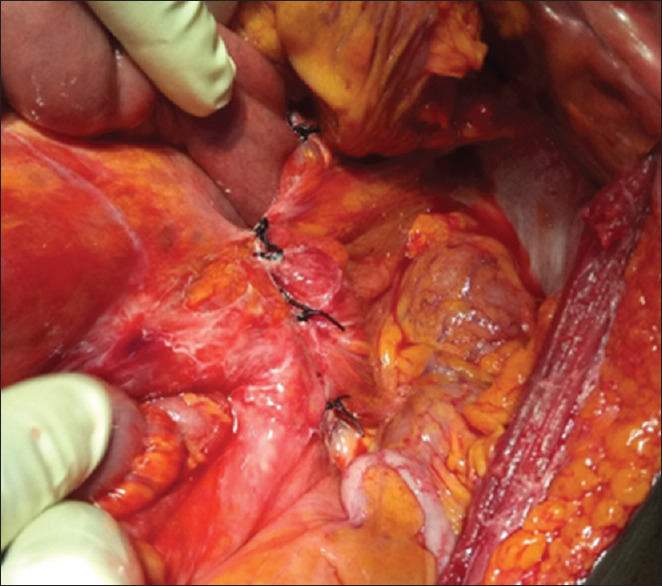

十二指肠旁疝是先天性的,可能表现为小肠梗阻的症状和体征。这些疝气在我们的实践中是罕见的,由于症状不具体,通常不能做出明确的术前诊断。早期评估,及时和充分的复苏和手术可以避免窒息和肠切除术的风险。本文报告一例罕见的肠梗阻的年轻男性,他表现出肠梗阻的所有典型特征:绞痛腹痛、腹胀、呕吐、无法排便或放屁。术中诊断为十二指肠旁疝。在急性腹痛患者中,我们通常不要求进行钡剂检查或腹部计算机断层扫描。这些形态可以提示术前诊断。

Paraduodenal hernias are of congenital origin and may present with symptoms and signs of small intestinal obstruction. These hernias are rare in our practice, and a definitive preoperative diagnosis is often not made as the symptoms are not specific. Early assessment and prompt and adequate resuscitation and surgery obviate the risk of strangulation and intestinal resection. This report highlights a rare cause of intestinal obstruction in a young male who presents with all the classical features of obstruction: colicky abdominal pain, distension, vomiting, and inability to pass stool or flatus. The diagnosis of paraduodenal hernia was made intraoperatively. We do not routinely request for barium examination or abdominal computed tomography scan in acute abdominal pain. These modalities can suggest a preoperative diagnosis.